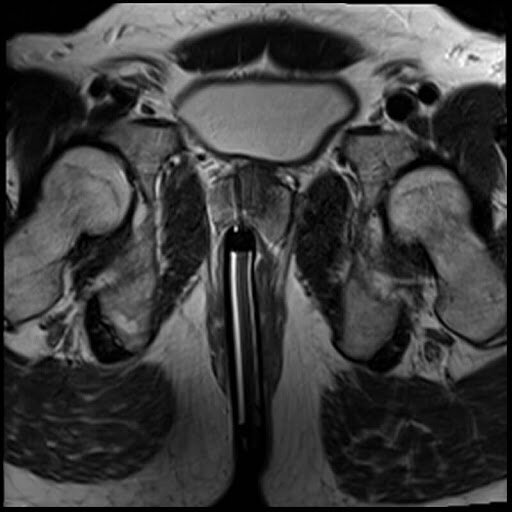

ПРИЗНАКИ АДЕНОМЫ ПРЕДСТАТЕЛЬНОЙ ЖЕЛЕЗЫ НА МРТ

Диагностика аденомы простаты в большинстве случаев осуществляется в ходе двойного ультразвукового обследования - ТРУЗИ и абдоминальное УЗИ. Необходимость сделать МРТ при аденоме возникает только, когда по результатам ультразвука у врача возникает подозрение, что образование может иметь злокачественный потенциал. Чтобы провести точную дифференциальную диагностику аденомы и рака простаты назначается сделать МРТ предстательной железы с контрастом. Такую магнитно-резонансную диагностику следует осуществлять в медицинских центрах с высокопольными томографами мощностью 1,5 Тесла и выше.

Признаками аденомы предстательной железы на МРТ будут:

• наличие образование с четкими краями;

• ненакпливание контрастного вещества в тканях образования;

• отсутствие инвазии в мочеиспускательный канал.